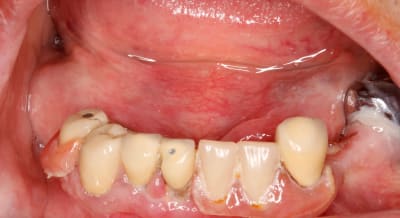

A priori patient édenté au maxillaire , ou bien une p'tite fatigue de ta part ce jour là . ;o)))))

Remarque : y z'ont aussi des clodos dans le personnel Air France ????? ce monde va mal !